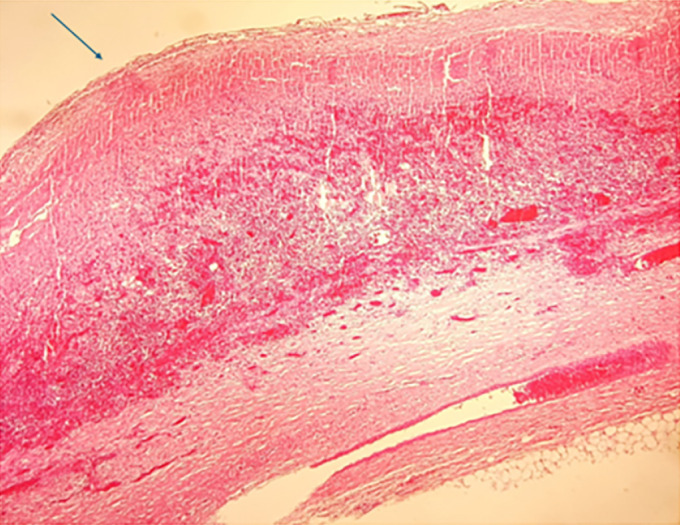

虽然罕见,但乳腺包虫病代表乳腺假瘤。我们提出的情况下,49岁的妇女没有明显的病史,谁被诊断为孤立的包虫囊肿的乳房组织病理检查证实。该患者因乳房不对称和左乳感觉沉重而就诊,无全身包虫病的临床体征。超声乳房x光检查提示诊断,术后组织病理检查证实。虽然很少报道,原发性乳腺包虫病可引起类似肿瘤的症状。手术切除被证明是治疗这种类型乳腺囊肿的有效方法。

Although rare, a hydatid cyst of the breast represents a mammary pseudotumor. We present the case of a 49-year-old woman with no significant medical history, who was diagnosed with an isolated hydatid cyst of the breast confirmed by histopathological examination. This patient consulted for breast asymmetry and a feeling of heaviness in the left breast, with no clinical signs of systemic hydatidosis. The diagnosis was suggested by echo-mammography and confirmed postoperatively by histopathological examination. Although rarely reported, primary hydatid cyst of the breast can cause symptoms that mimic neoplasia. Surgical excision alone proved effective in treating this type of breast cyst.